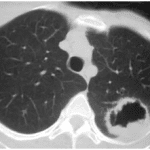

Lung Cancer

Introduction When we talk about lung cancer, we are generally referring to tumour of the bronchus. 95% of lung cancers are carcinoma of the bronchus 2% are alveolar tumours 3%…